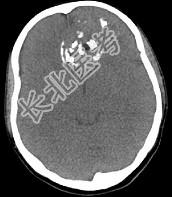

- 多项选择题男性,28岁, 因鼻塞、头痛1年余,鼻窦CT扫描如图所示, 请选择正确的描述与结论 ( )

A、双侧上颌窦、筛窦、鼻腔及蝶窦内见软组织肿块影

B、肿块内密度不均,有较多致密钙化影

C、窦壁及颅底骨质破坏